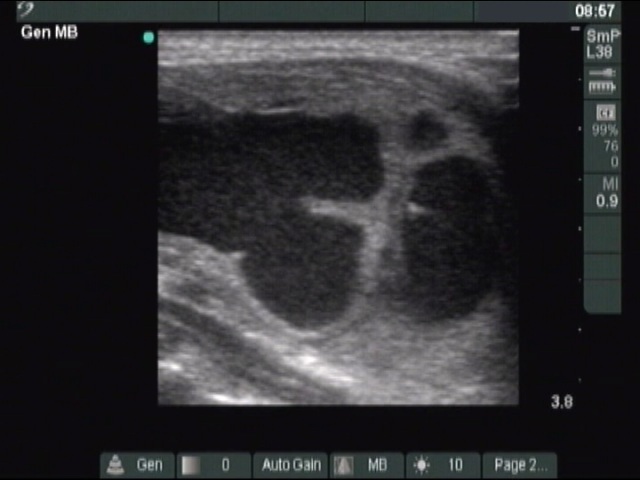

Ultrasonography: The thyroid was echonormal. A large cystic nodule composed of multiple chambers occupied almost the entire right lobe. Several fibrotic bundles dividing the chambers of the cyst were ruptured. The nodule presented halo sign and perinodular blood flow.